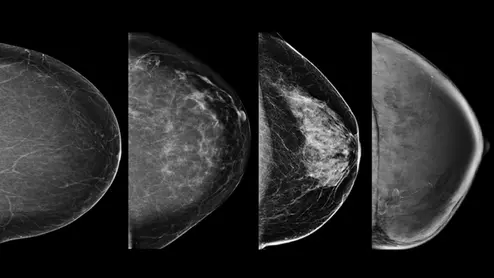

Example of the four types of breast tissue density. The density of fibroglandular tissue inside the breast impacts the ability to easily see cancers. Cancers are very easy to spot in fatty breasts, but are almost impossible to find in extremely dense breasts. These examples show craniocaudal mammogram findings characterized as almost entirely fatty (far left), scattered areas of fibroglandular density (second from left), heterogeneously dense (second from right), and extremely dense (far right). RSNA